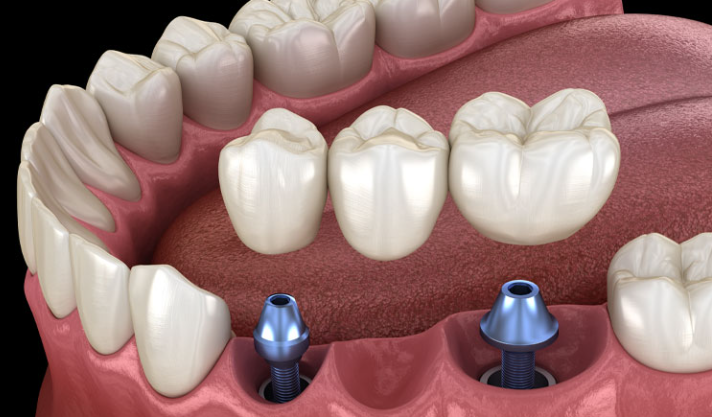

어금니 임플란트 과정

어금니 임플란트 비용을 확인한 후, 이제 어금니 임플란트의 전체 과정에 대해 상세히 알아보겠습니다. 일반적으로 다음과 같은 몇 가지 단계로 진행됩니다. 전체 과정은 환자의 건강 상태, 필요한 임플란트 수, 대체할 어금니의 위치 등에 따라 약간의 변동이 있을 수 있습니다.

2단계 - 수술: 치과 의사는 어금니 부위에 구멍을 내고 임플란트를 천천히 삽입합니다. 그 후, 임플란트 주위의 뼈와 임플란트가 잘 결합되도록 치유를 위한 기간을 대기합니다. 이는 일반적으로 몇 주에서 몇 개월까지 걸릴 수 있습니다.

3단계 - 임시 크라운 설치: 치유 과정 후, 임플란트 주위의 뼈와 임플란트가 충분히 결합되었다고 판단되면 임시 크라운을 임플란트에 부착합니다. 이로써 환자는 일상적인 식사와 말하기를 할 수 있게 됩니다.

4단계 - 영구 크라운 설치: 뼈와 임플란트가 완전히 결합된 후, 임시 크라운을 제거하고 영구 크라운을 설치합니다. 이 과정에서는 어금니의 자연스러운 외관과 느낌을 제공하며, 장기적으로 안정성과 기능성을 보장합니다.